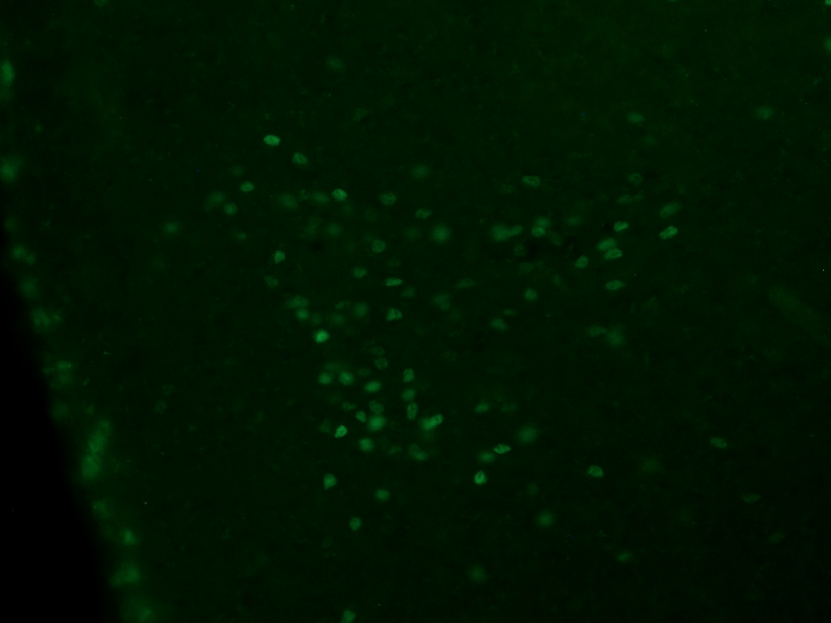

(a) Green image example

Figure 2: Data preview. The figures show examples of fluorescence micrscopy pictures (Figures 2(a), 2(b) and 2(c)) and the corresponding ground-truth binary masks (Figures 2(d), 2(e) and 2(f)).

More specifically, the green collection corresponds to cFOS staining (cf. Figure 2(d)). This staining method was employed to emphasize the nuclei of active neuronal cells[18], enabling the topographic analysis of brain areas that exhibit neuronal activity under specific experimental conditions. This approach is widely employed to identify neuronal cells responsible for regulating specific physiological phenomena.

Peculiar traits

In all image collections, the visual representation is characterized by the prevalence of two distinct color tones, which result from the deliberate selection of a specific wavelength. One tone appears darker, indicating areas where light has been filtered out, while the other tone is brighter and more intense, emitted by the fluorophore corresponding to the color of each collection (see Figures 2(a), 2(b) and 2(c)). As a result, the images can generally be depicted using variations of a single color. Consequently, a 1-D representation may be sufficient, or an alternative color space other than RGB could provide more informative and less redundant data.